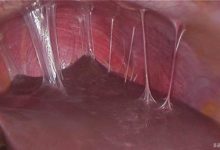

Akut salpenjitte, fallop tüpleri şişer, iltihaplanır ve aşırı miktarda sıvı salgılarlar, bu da iç duvarlarının birbirine yapışmasına neden olabilir. Daha şiddetli vakalarda, fallop tüpleri bağırsak gibi yakındaki yapılara yapışabilir.

Bazen bir fallop tüpü irinle dolabilir ve şişebilir. Enfekte fallop tüpü nadiren de olsa koparsa, karın boşluğunun tehlikeli bir enfeksiyonuna (peritonit) neden olur.